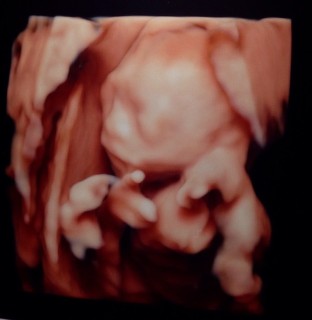

胎児ドックの際、ソッポ向いてなかなか顔を見せてくれず、足踏みしたり散歩したりしてやっとこっちを向いてくれた時の写真。なんで「ゲッツ!」してるのかなぁ(笑)どうだイケメンだろぉ?ってアピールしてるのかな?(笑)とりあえず可愛かったです。重さは240gで問題なし(>∀<)